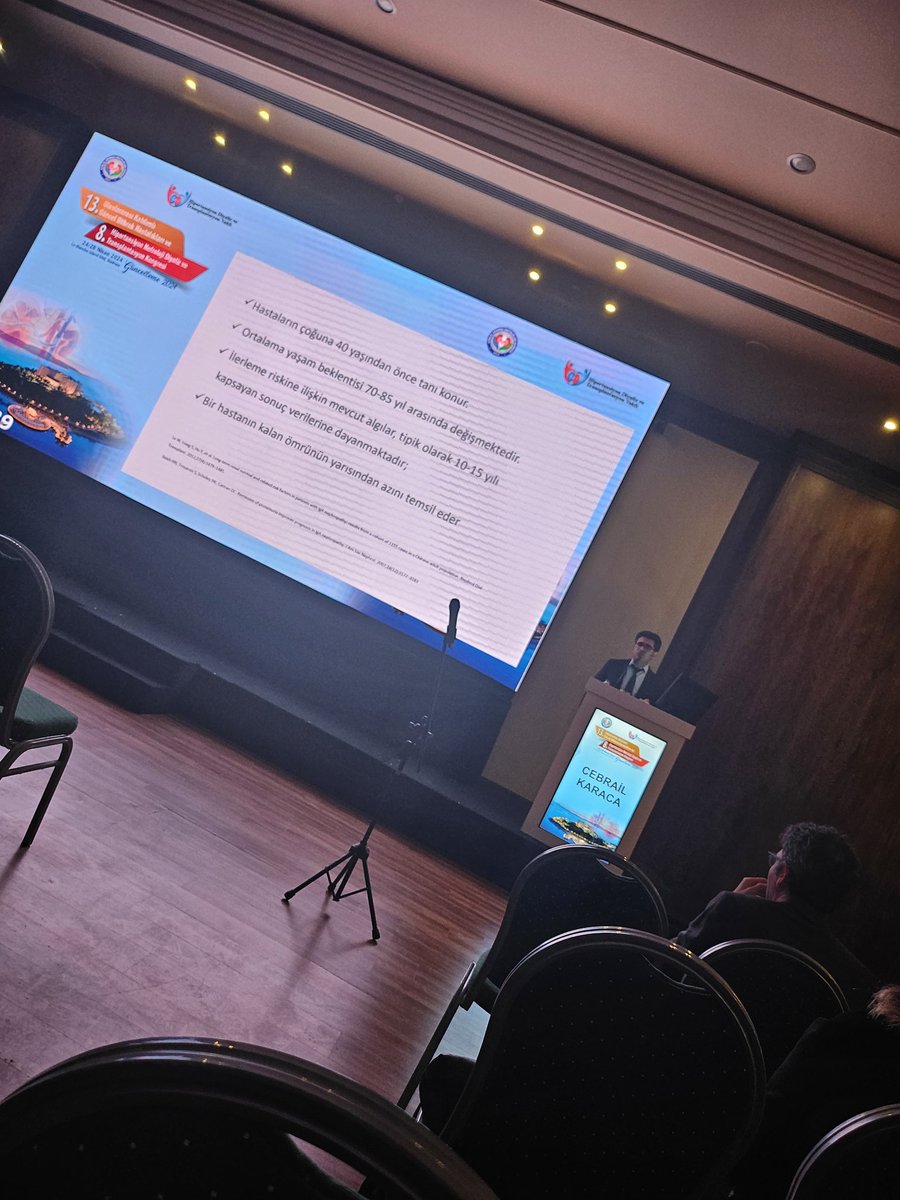

13th Annual Meeting of Contemporary Issues in Renal Diseases with International Participation & 8th Congress of Hypertension Nephrology Dialysis and Transplantation; young nephrologists session; discussing literature👏👏👏👏 Ahmet Murt Tamer Dincer, Cebrail Karaca, Omer Akçay